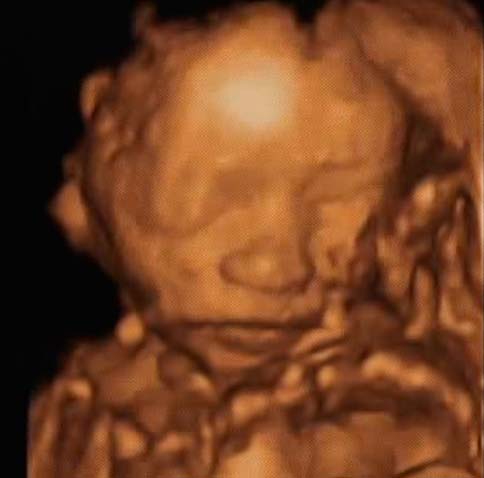

Les proportions du corps fœtal sont près de 100% proches des paramètres du nouveau-né. La seule différence est que le bébé a l'air mince, avec des bras et des jambes très fins et une peau ridée. En effet, la couche de graisse sous-cutanée n'est pas complètement formée.

Voici à quoi ressemble le fœtus à 24 semaines:

À ce moment, l'échographie est rarement prescrite. Mais si vous allez à cette étude, vous pouvez certainement voir le visage de votre enfant. Ses caractéristiques ne changeront pas jusqu'à la naissance même.

Photo échographie: